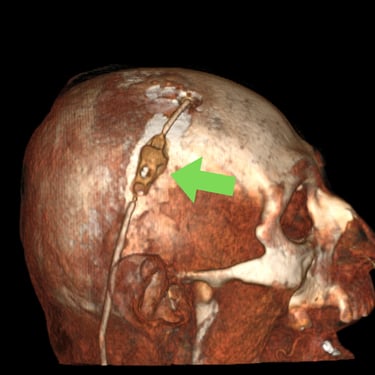

Hidrocefalia – Colocación de derivación ventriculoperitoneal (DVP).

La hidrocefalia es una condición neurológica causada por la acumulación anormal de líquido cefalorraquídeo dentro de los ventrículos cerebrales, lo que genera aumento de la presión intracraneal y deterioro neurológico progresivo. La colocación de una derivación ventrículoperitoneal (DVP) es el tratamiento quirúrgico más utilizado para controlar esta patología. Este sistema permite drenar el exceso de líquido desde el cerebro hacia la cavidad abdominal, donde se reabsorbe de manera segura. La intervención oportuna alivia los síntomas, previene daño cerebral y mejora la calidad de vida del paciente.